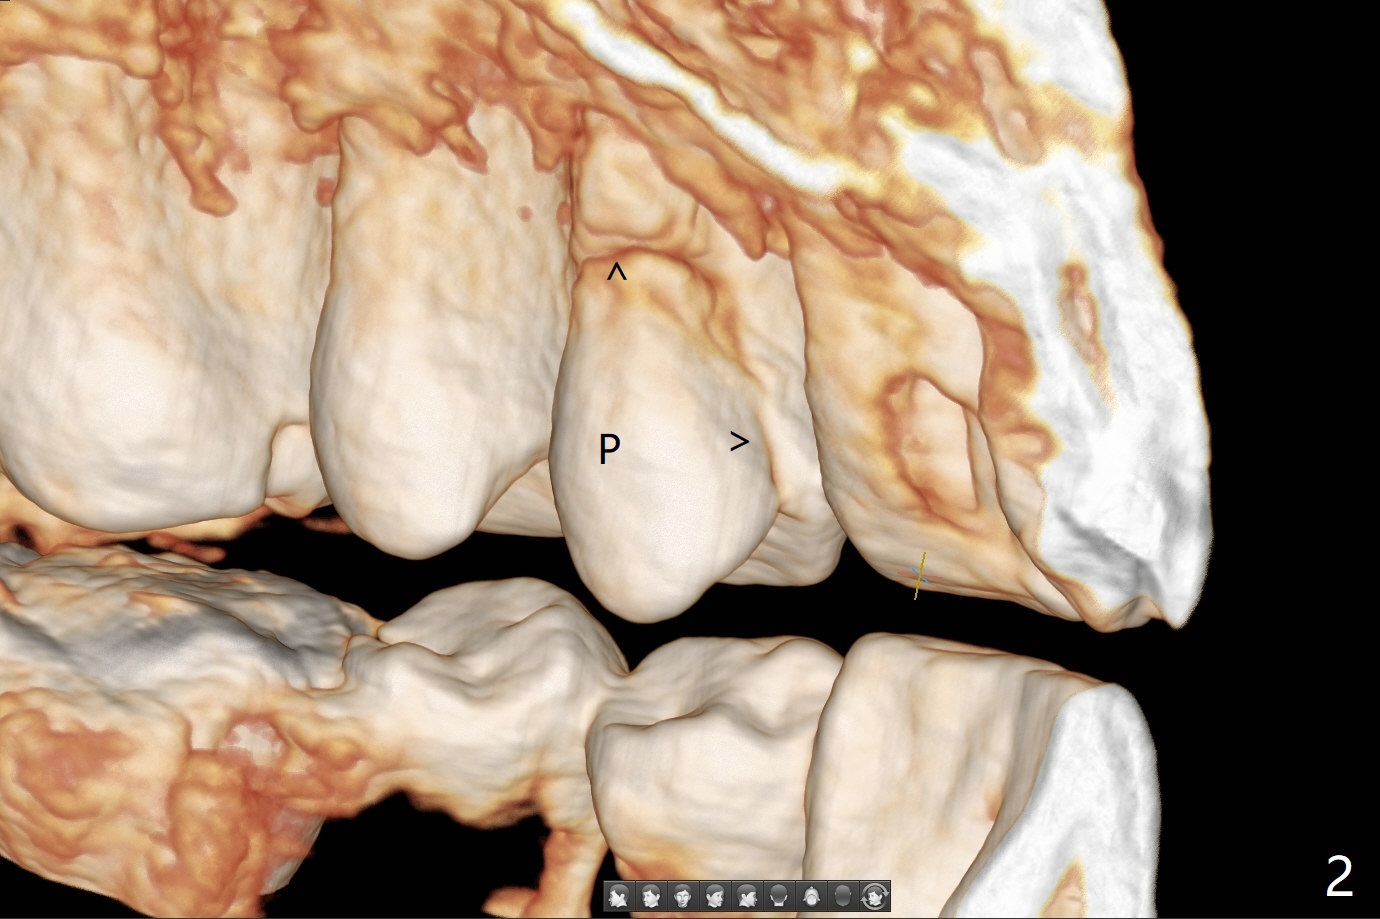

46岁男(每天两包烟,同意术前术后几天不吸烟)左上第一双尖牙折裂(图一,二(CT 3-D图)),由于折裂穿过牙髓(图三),摇动腭侧(P)断片特别痛。拔除患牙后(图四:黑色),由于窦底薄(图四:^),用锥形骨凿提升(图五(窦膜厚:黄虚线)),放置粘性骨粉后(图六),在牙槽窝腭侧骨壁中间开始钻洞(图七:红箭头),钻头尖一旦进入骨板,马上改变钻洞方向,与修复一致,然后穿过窦底(图八:绿箭头)由于窦膜已经提升,穿过窦底谅必安全。最后植入4x14或者17毫米软组织水平植体(图九),准备4毫米报废植体。Return to Protect Graft Clindamycin 前磨牙即种 Xin Wei, DDS, PhD, MS 1st edition 05/01/2021, last revision 05/03/2021